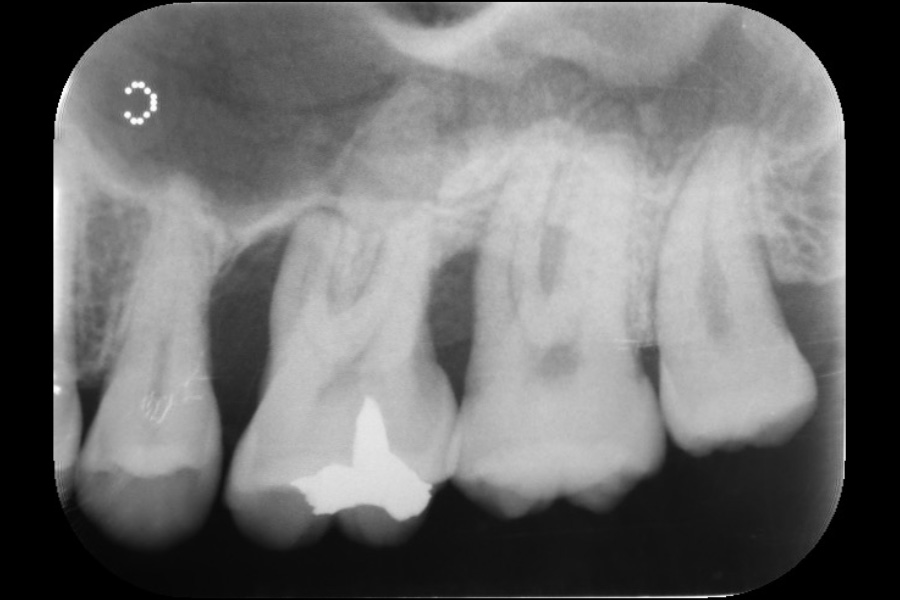

下の前歯から出血する

【歯周組織再生療法】

- 主訴

- 下の前歯から出血する

- 治療内容

- 左下2遠心に垂直性骨吸収が認められたためエムドゲインと骨補填材を用いて歯周組織再生療法を行った

- 治療に伴うリスク

- 歯肉退縮、知覚過敏